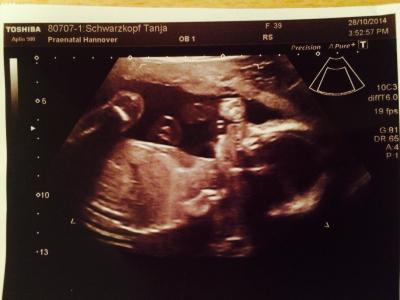

Hallo ihr Lieben, Heute waren wir zur Feindiagnostik. Nachdem ich Freitag abends wieder Schmierblutungen hatte die ich im KH abklären ließ, hätte ich heute echt etwas Angst vor der Untersuchung. Aber alles zeitgerecht entwickelt. Leon ist etwa 25 cm groß und etwa 480 Gramm schwer. Den Schniepel hat er auch voll ins Bild gestreckt. Mein Mann hinterher er hatte voll ne Latte. Hihi. Nur sein Gesicht wollte er nicht von vorne zeigen. Der Arzt sieht aber kein Risiko. Bin echt erleichtert. Anbei ein schönes Foto.

Bild zu Heute Feindiagnostik - Forum für März - Mamis